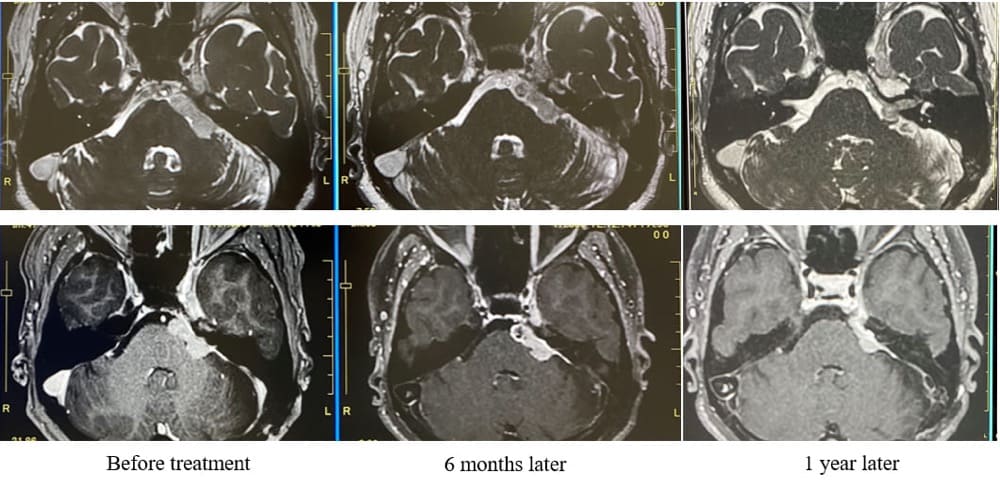

非典型的髄膜腫ZAP-X治療後症例の

経時的変化(脳幹症状・顔面麻痺なし)